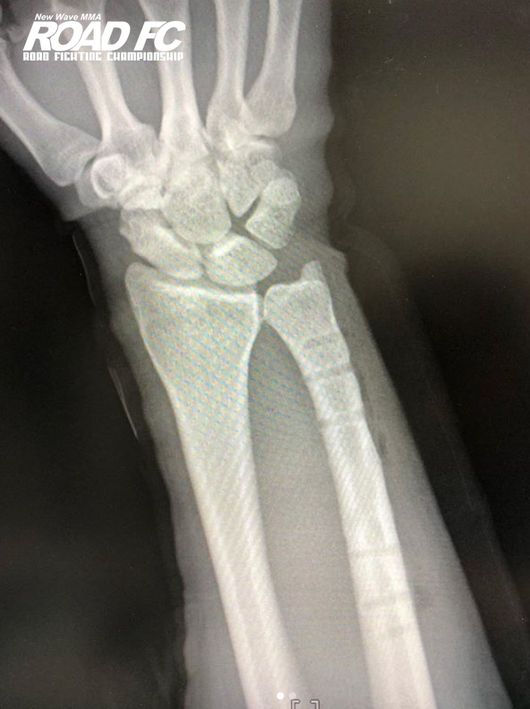

경기 후 함서희는 부산에서 팀 연말 파티에 참석하며 연말을 보냈고, 2019년이 돼서는 수술을 했다. 부상으로 다친 팔에 있는 핀을 제거, 이제 완벽히 회복할 날만을 기다리고 있다.

“다쳤던 팔에 핀을 제거하는 수술을 최근에 하고 회복하고 있다. 안에 뼈가 차야 하는데, (회복에 얼마나 걸릴지) 정확히 모르겠다. 그래도 이 손만 못쓸 뿐이지 다른 곳은 멀쩡하니까 운동을 쉬지 않을 거 같다” 함서희의 말이다.